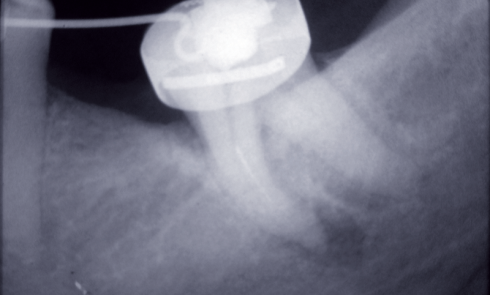

Endodontie

Article réservé à nos abonnés Us et abus des antibiotiques en endodontie (1/3)

En endodontie, les antibiotiques sont utiles quand il est nécessaire d’aider les défenses de l’hôte à éliminer les micro-organismes résiduels...